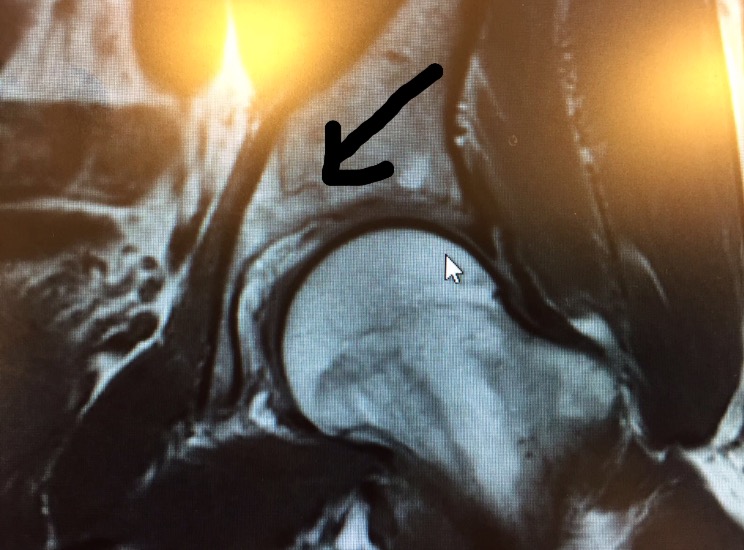

Muutamaa päivää myöhemmin magneetissa todettiin lantiossa hyväasentoinen murtuma. Reisiluun pää oli tärähtänyt kuopan pohjaan niin kovaa, että nivelkuppi oli haljennut pitkälle lantioon. 6 viikkoa kepeillä, 2,5 kuukauden juoksukielto. Uutinen oli musertava, Hawaji ja Konan Ironman oli auttamatta menetetty. En ole urheilu, enkä matkustuskunnossa, teräsmiehestä yhtäkkiä täysin liikunta-kyvyttömäksi keppipotilaaksi. Muutama viikko sitten itkin onnesta Kalmarissa ja nyt itken menetetystä mahdollisuudesta . Ei paljoa urheilun antamaa draamaa voisi olla enempää…